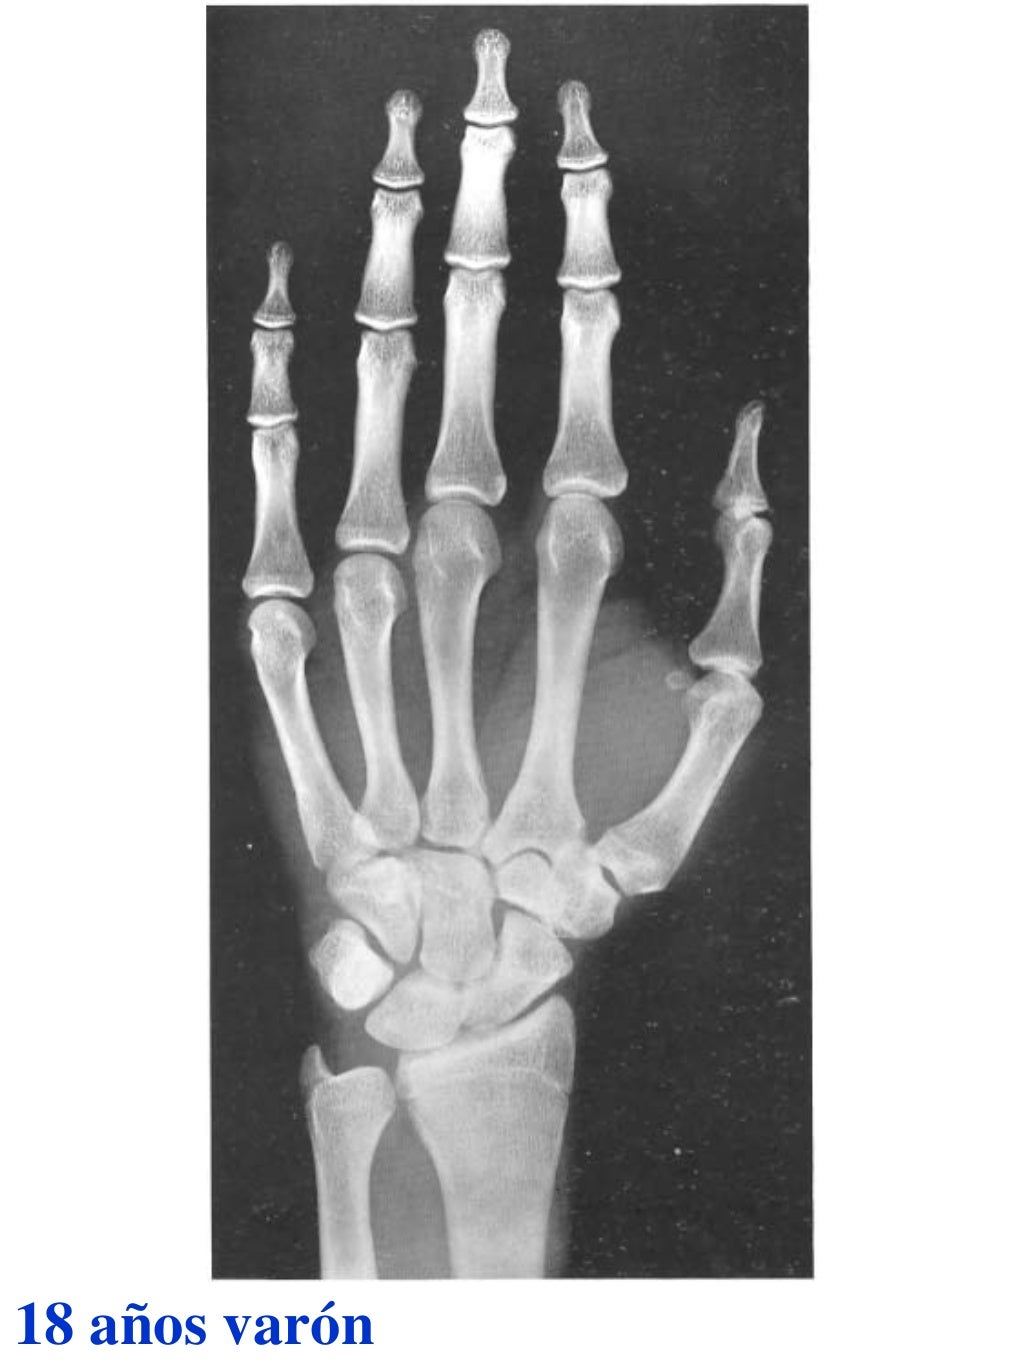

Tablas De Greulich Y Pyle The standards established by greulich and pyle, undoubtedly the most popular method, consist of two series of standard plates. The standards established by greulich and pyle, undoubtedly the most popular method, consist of two series of standard plates. El documento lista las edades. This systematic review summarizes the. The greulich and pyle method is one of the two main ways to assess the bone age of children. Both main methods of bone age. Scribd is the world's largest social reading and publishing site. 153 recomendaciones • 616,869 vistas. Atlas greulich y pyle | pdf | descarga gratuita. The greulich and pyle atlas is used to estimate the age of children and adolescents. The radiographic atlas of skeletal development of the hand and wrist by ww greulich and si pyle is a classic radiological.

Atlas greulich y pyle Tablas De Greulich Y Pyle The standards established by greulich and pyle, undoubtedly the most popular method, consist of two series of standard plates. Atlas greulich y pyle | pdf | descarga gratuita. Scribd is the world's largest social reading and publishing site. 153 recomendaciones • 616,869 vistas. The radiographic atlas of skeletal development of the hand and wrist by ww greulich and si pyle. Tablas De Greulich Y Pyle.